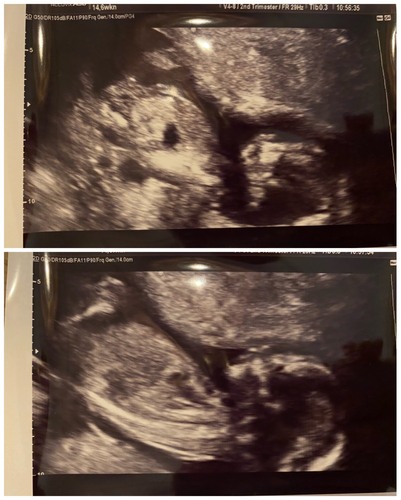

14+6 weken

Hii! Ik vraag me af of jullie het kunnen zien of dit een jongetje of een meisje is? 馃槉